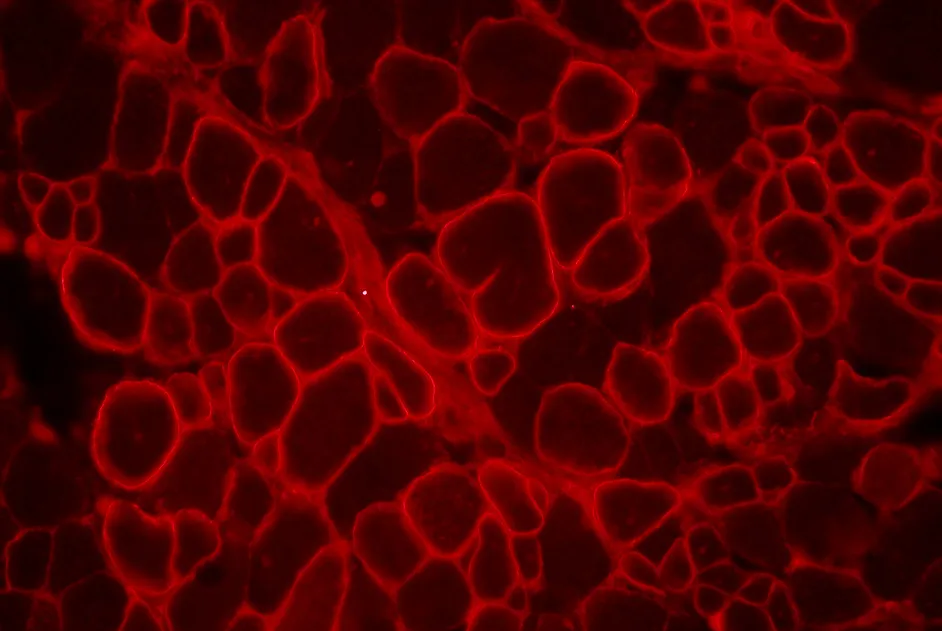

L’expression de la dystrophine a été rétablie et a permis d’augmenter la différenciation des myoblastes. L’expression de micro ARN (des petits ARN endogènes, non codants, qui régulent l’expression de gènes en bloquant leur traduction en protéine), perturbée dans la DMD, a également été rétablie et la NO synthase (l’enzyme responsable de la synthèse de l’oxyde nitrique (NO)) a été relocalisée à la membrane.